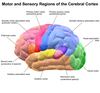

Grey Matter communicates _____ information

Sensorimotor

White Matter (Corpus Callosm)

Myelinated (Communicate between hemispheres)

Limbic System integrate emotions and regulate motivated

learning and behavior

Hippocampus is involved in these type of memories

New & long term

Nucleui Accumbens (Limibic System)

Reinforces Reward (VTA/Mesolimbic pathways)

Amygdala (Temporal Lobe)

Coordinate

Emotional Response and Memories

Dopamine is found in the

Substania Nigra and VTA